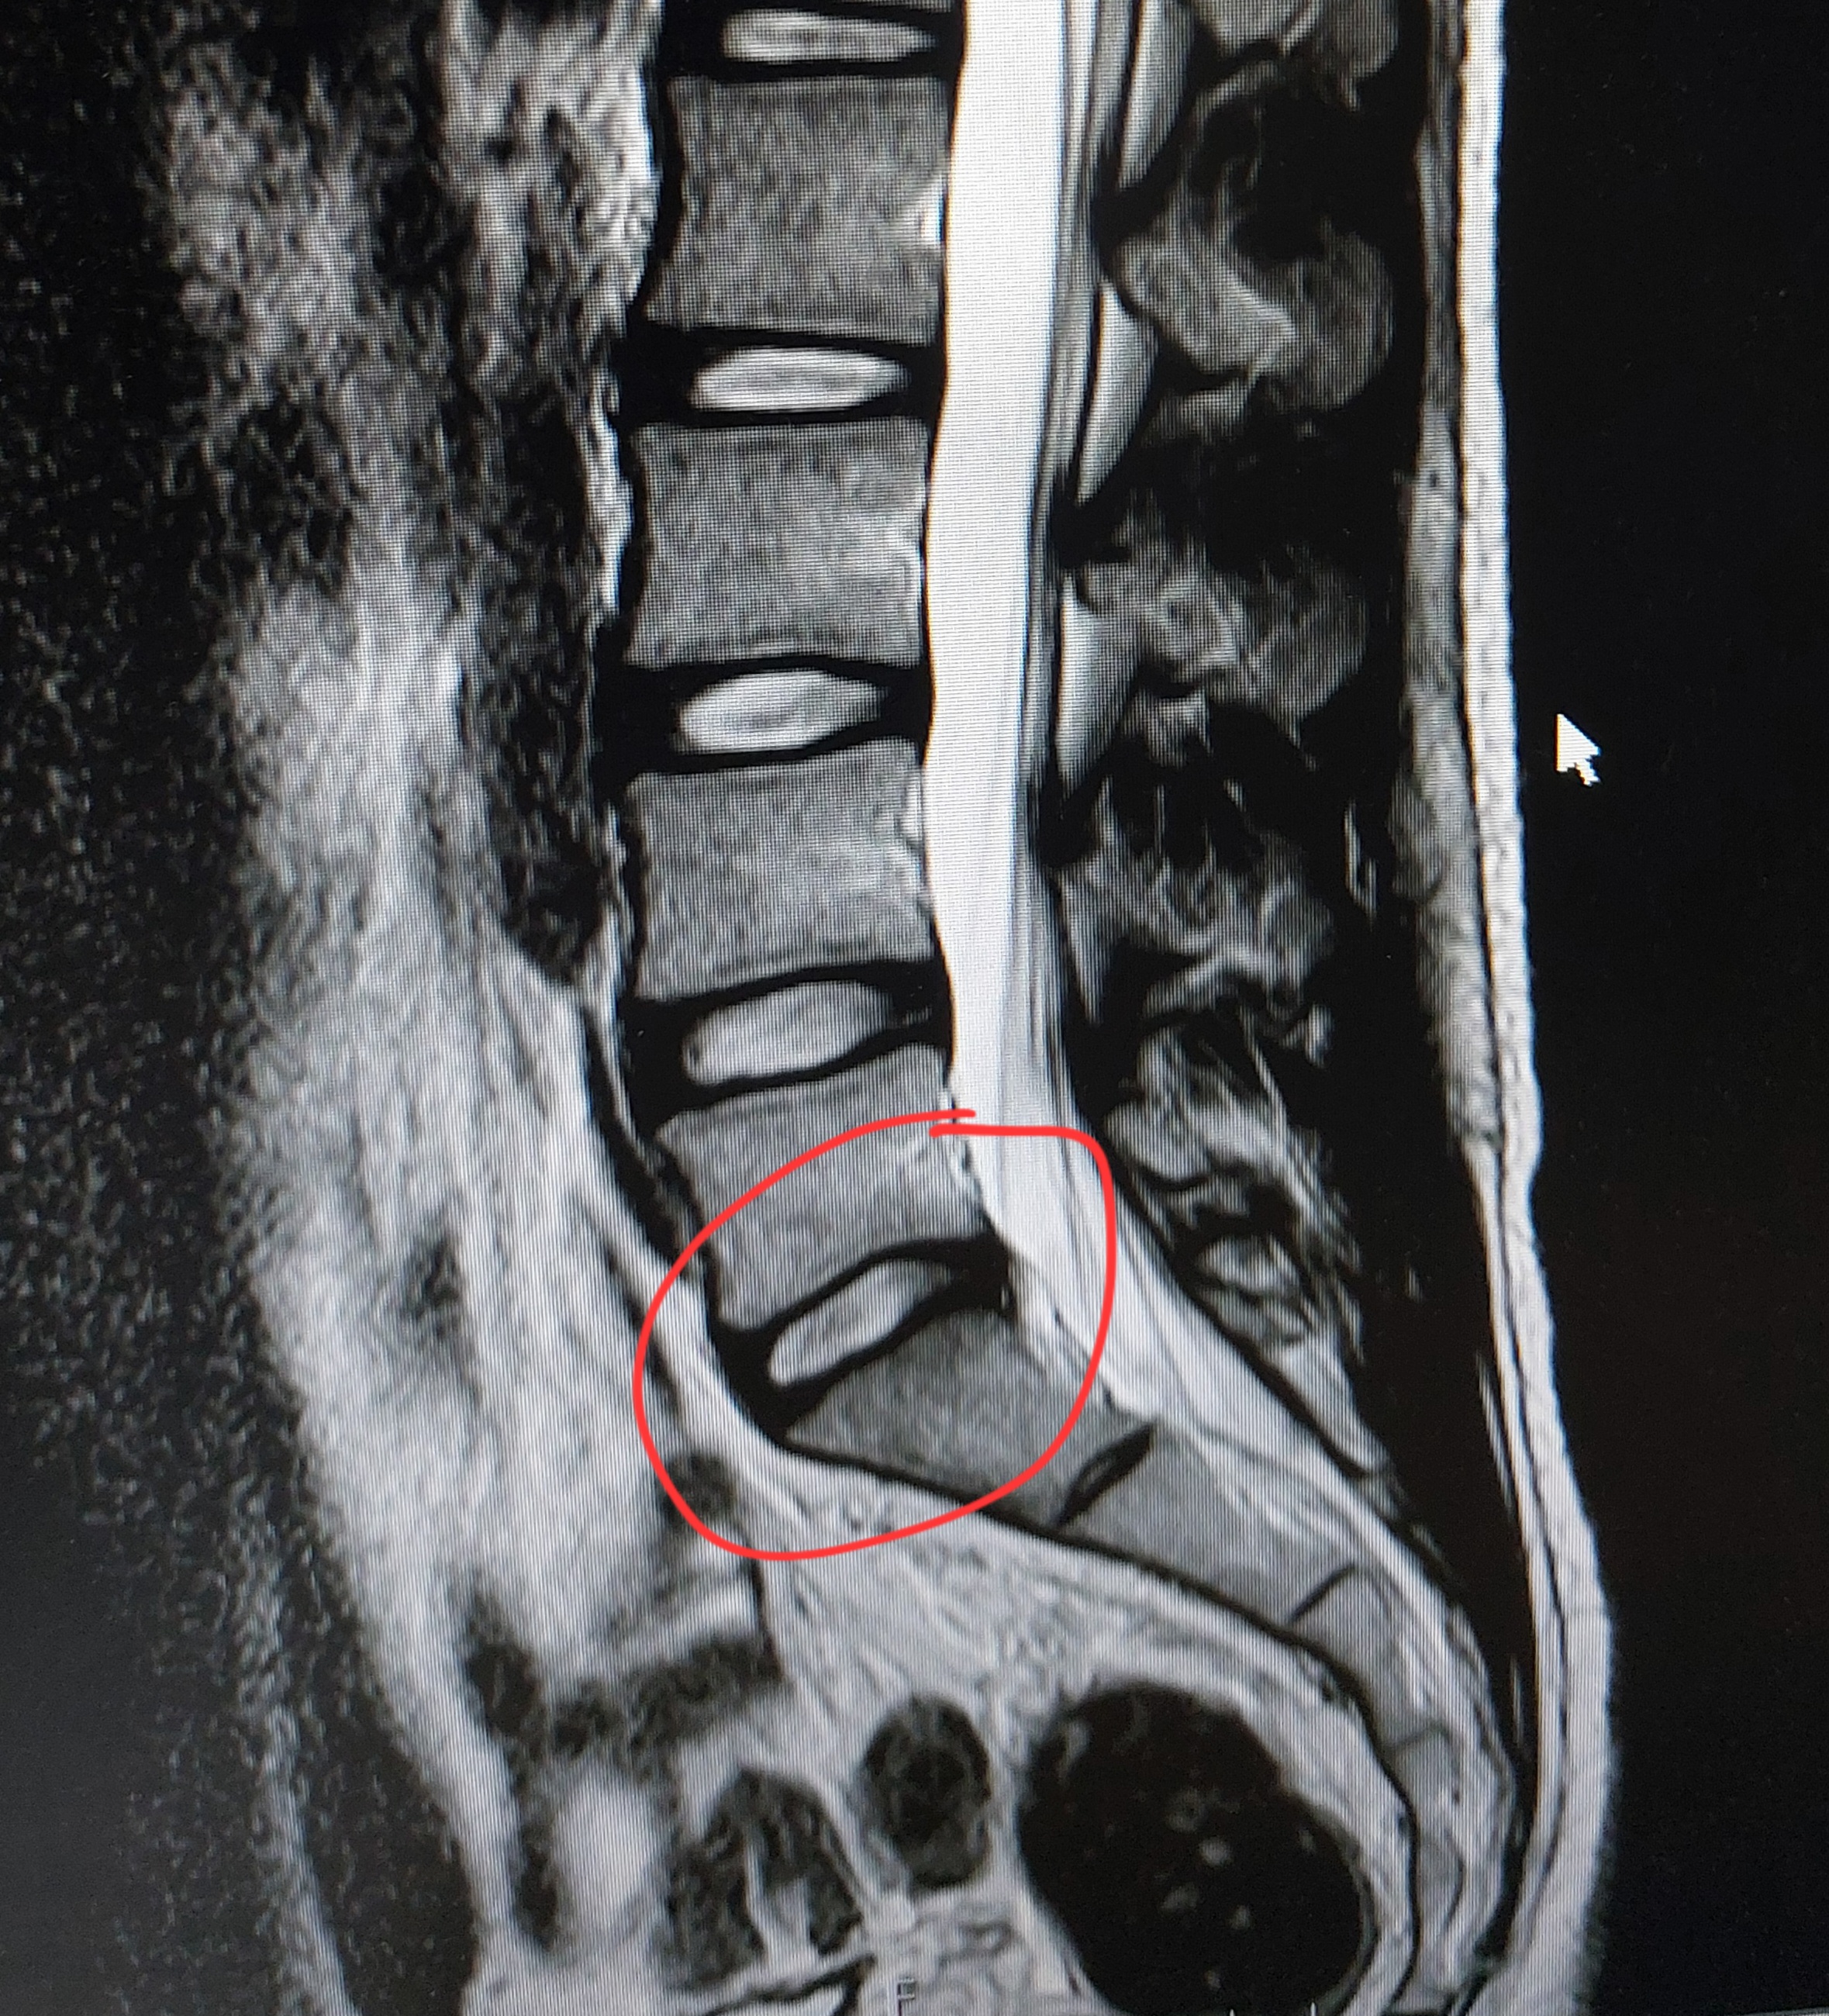

허리디스크 심한편인가요? [Mri 사진 첨부]

멸개월전부터 요추가 뻣뻣하고 시큰거리다가 최근에 좀 나아지긴 해도 만성적이라서 오늘 mri 찍고 허리디스크 진단받았습니다

(요추 맨 밑 천추 위 디스크)

Mri 찍은 병원은 고주파 시술같은거 하라고 하고 다른병원은 이정도면 잘 쉬면 완치된다고 하는데

1. 이정도면 정상수준이라고 하는 분도 있던데 어느정도 수준인가요?

신경이 심하게 눌리고 있지는 않은 것으로 보입니다. 충분히 휴식하여 주시고, 허리에 무리가 많이가는 자세는 당분간은 피해주시는 것이 좋습니다.